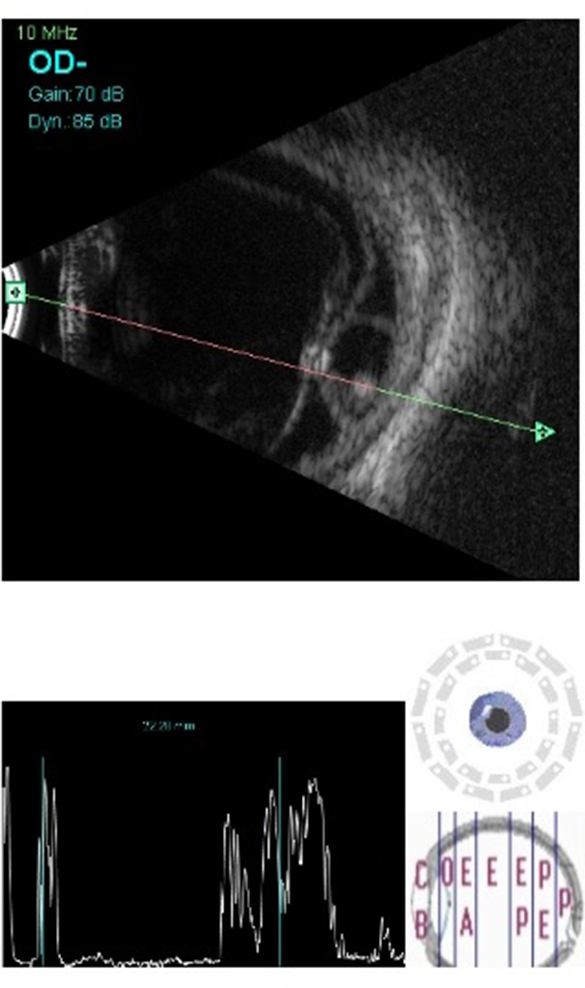

OD B-scan showed multiple membrane echoes of moderate to high intensity in the anterior vitreous with a hyperechoic central shadow moving with movement of the eye ball suggestive of dense vitreous membranes with scolex, an area of high intensity echoes at low gain at inferior temporal quadrant suggestive of retinal detachment and underneath it, a well-defined cystic lesion with clear contents and a hyperechoic shadow suggestive of a scolex (Figure 1 [Fig. 1] and Figure 2 [Fig. 2]). Orbital ultrasonography (USG) revealed no cystic lesions in the orbit or extraocular muscle. Stool examination, ELISA for serum antibodies (IgG) and CT scan brain was done, and neurocysticercosis was ruled out.

Figure 1: B-scan ultrasound of the posterior segment of the right eye showing inferotemporal retinal detachment with a well-defined subretinal cyst having high amplitude, dot-like echo suggestive of scolex. Hyperechoic dot with high amplitude spike in vitreous cavity suggestive of another scolex